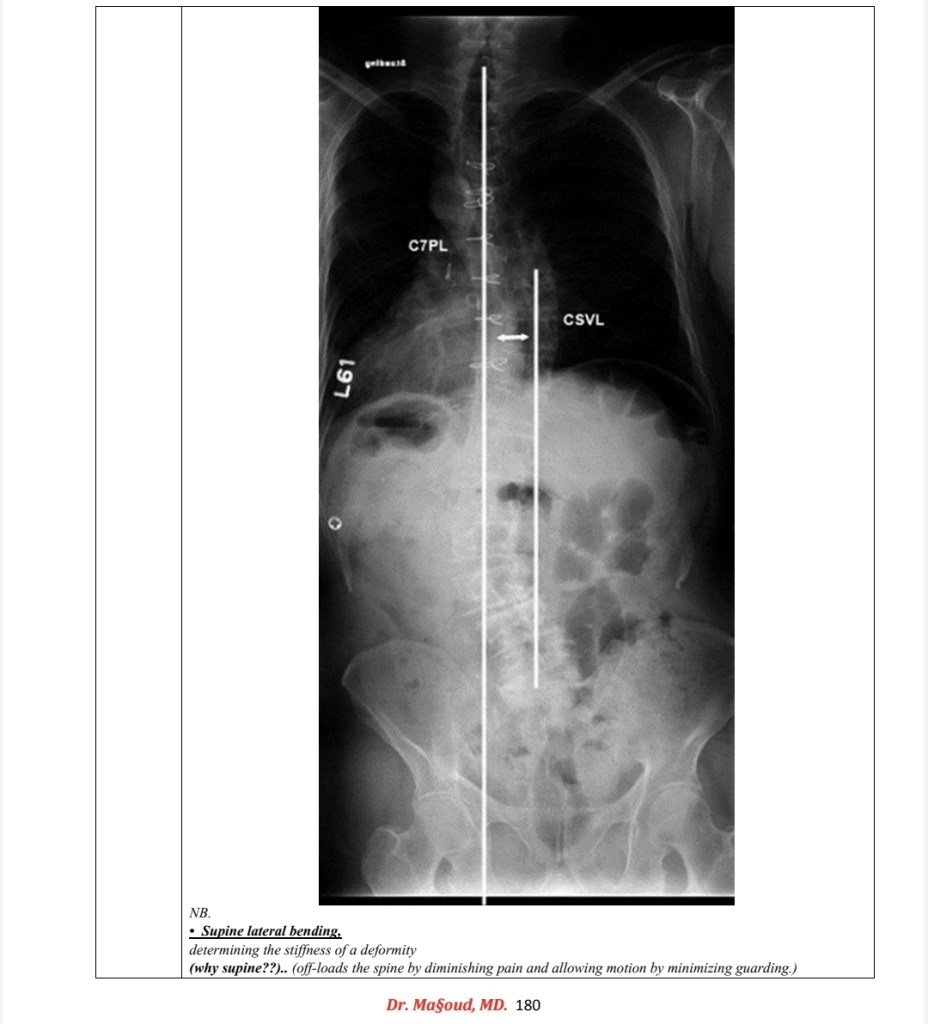

Spine imaging